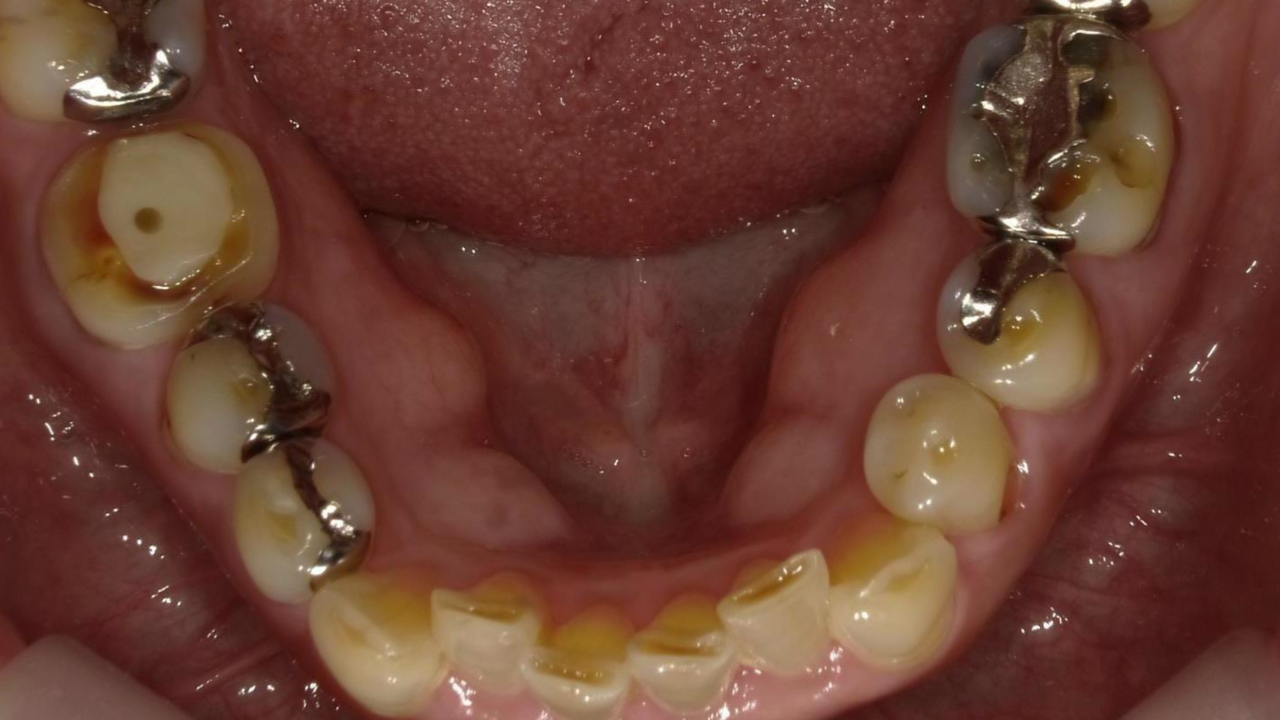

N・H様 女性 70代

Before

After

右下奥歯が噛むと痛くなり、来院されました。レントゲンで歯の根が破折しており、抜歯となりました。抜歯後にインプラント治療を希望され治療を開始。治療後、違和感もなく奥歯で何でも食べれるようになったと満足されていました。

治療期間・回数:11か月、18回

治療の価格:インプラント治療  550,000円 (上部構造含む)

治療のリスクや副作用:手術後に、痛みや腫れ、出血、合併症などを引き起こす可能性があります。噛む感覚がご自身の歯と異なる場合があります。見た目がご自身の歯と異なる場合があります。手術後にメインテナンスを継続しないと、インプラントが脱落するリスクがあります。